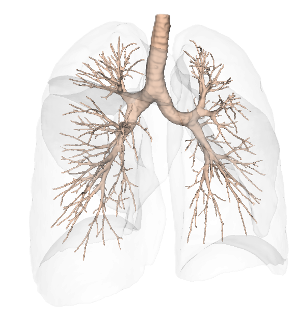

Bronchial tree

Anatomical segmentation

Advanced airway segmentation for navigational bronchoscopy planning

Recent studies demonstrate that LungQ®’s airway segmentation now matches and potentially surpasses expert-level manual assessment for bronchoscopy planning. By achieving subcentimeter alignment with expert-marked routes alongside fewer missed bifurcations, the AI tool provides a level of planning accuracy previously only mastered by experienced clinicians.

This evidence marks a major milestone in navigational bronchoscopy. By standardizing high-quality planning, LungQ® has the potential to broaden access to advanced navigational bronchoscopy, empowering clinical settings everywhere to deliver expert-level results at scale independent of local experience.

Quality of CT based airway segmentation software for navigation bronchoscopy